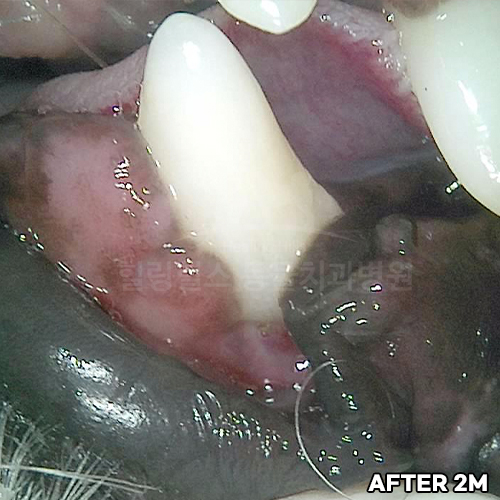

최고 난이도 강아지신경치료 - 꽉막힌 근관&치수괴사! 커다란 반려견치근단농양! 녹아내린 턱뼈! 치통으로 사나워진 모습! 강아지 신경치료 & 치주치료 한달 뒤 좋아졌어요!